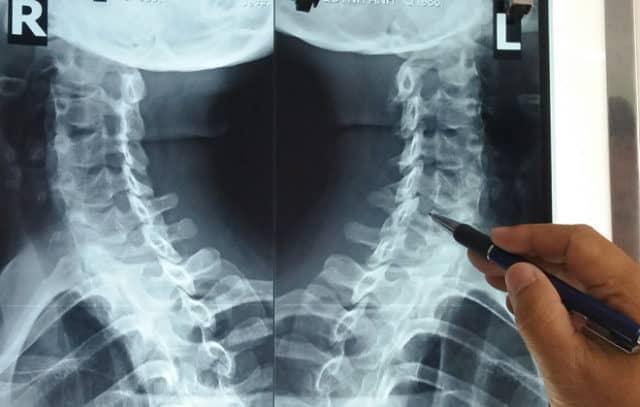

- Xét nghiệm hình ảnh: Bao gồm chụp X-quang vùng cổ, chụp cắt lớp (CT), chụp cộng hưởng từ (MRI) hoặc chụp tủy cổ cản quang để quan sát hình ảnh thoái hóa đốt sống cổ (nếu có).